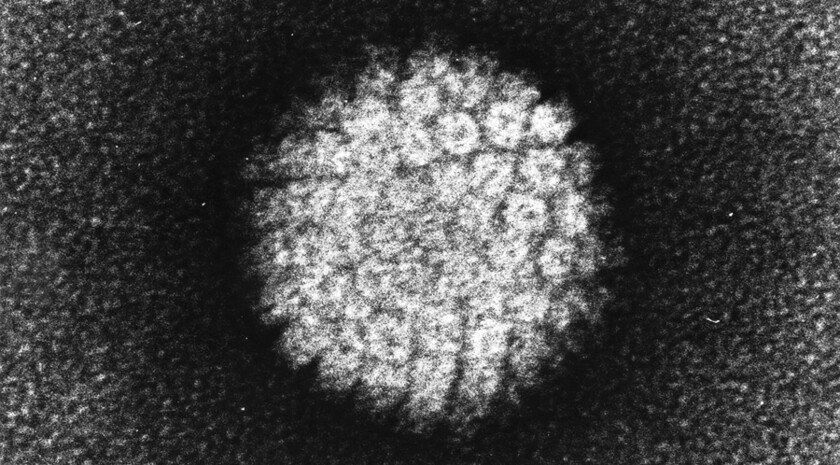

В России запущено полномасштабное производство первой отечественной вакцины против ВПЧФармацевтическая компания «Нанолек» при участии Фонда развития промышленности открыла в Кировской области первое в России производство вакцины против...